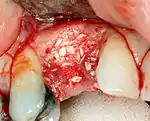

Additional procedures to augment deficient bone in implant site

For an implant to osseointegrate, it needs to be surrounded by a healthy quantity of bone. In order for it to survive long-term, it needs to have a thick healthy soft tissue (gingiva) envelope around it. It is common for either the bone or soft tissue to be so deficient that the surgeon needs to reconstruct it either before or during implant placement.[32]: 1084

Hard tissue (bone) reconstruction

Bone grafting is necessary when there is a lack of bone. Also, it helps to stabilize the implant by increasing survival of the implant and decreasing marginal bone level loss.[41] While there are always new implant types, such as short implants, and techniques to allow compromise, a general treatment goal is to have a minimum of 10 mm (0.39 in) in bone height, and 6 mm (0.24 in) in width. Alternatively, bone defects are graded from A to D (A=10+ mm of bone, B=7–9 mm, C=4–6 mm and D=0–3 mm) where an implant's likelihood of osseointegrating is related to the grade of bone.[42]: 250

To achieve an adequate width and height of bone, various bone grafting techniques have been developed. The most frequently used is called guided bone graft augmentation where a defect is filled with either natural (harvested or autograft) bone or allograft (donor bone or synthetic bone substitute), covered with a semi-permeable membrane and allowed to heal. During the healing phase, natural bone replaces the graft forming a new bony base for the implant.[38]: 223